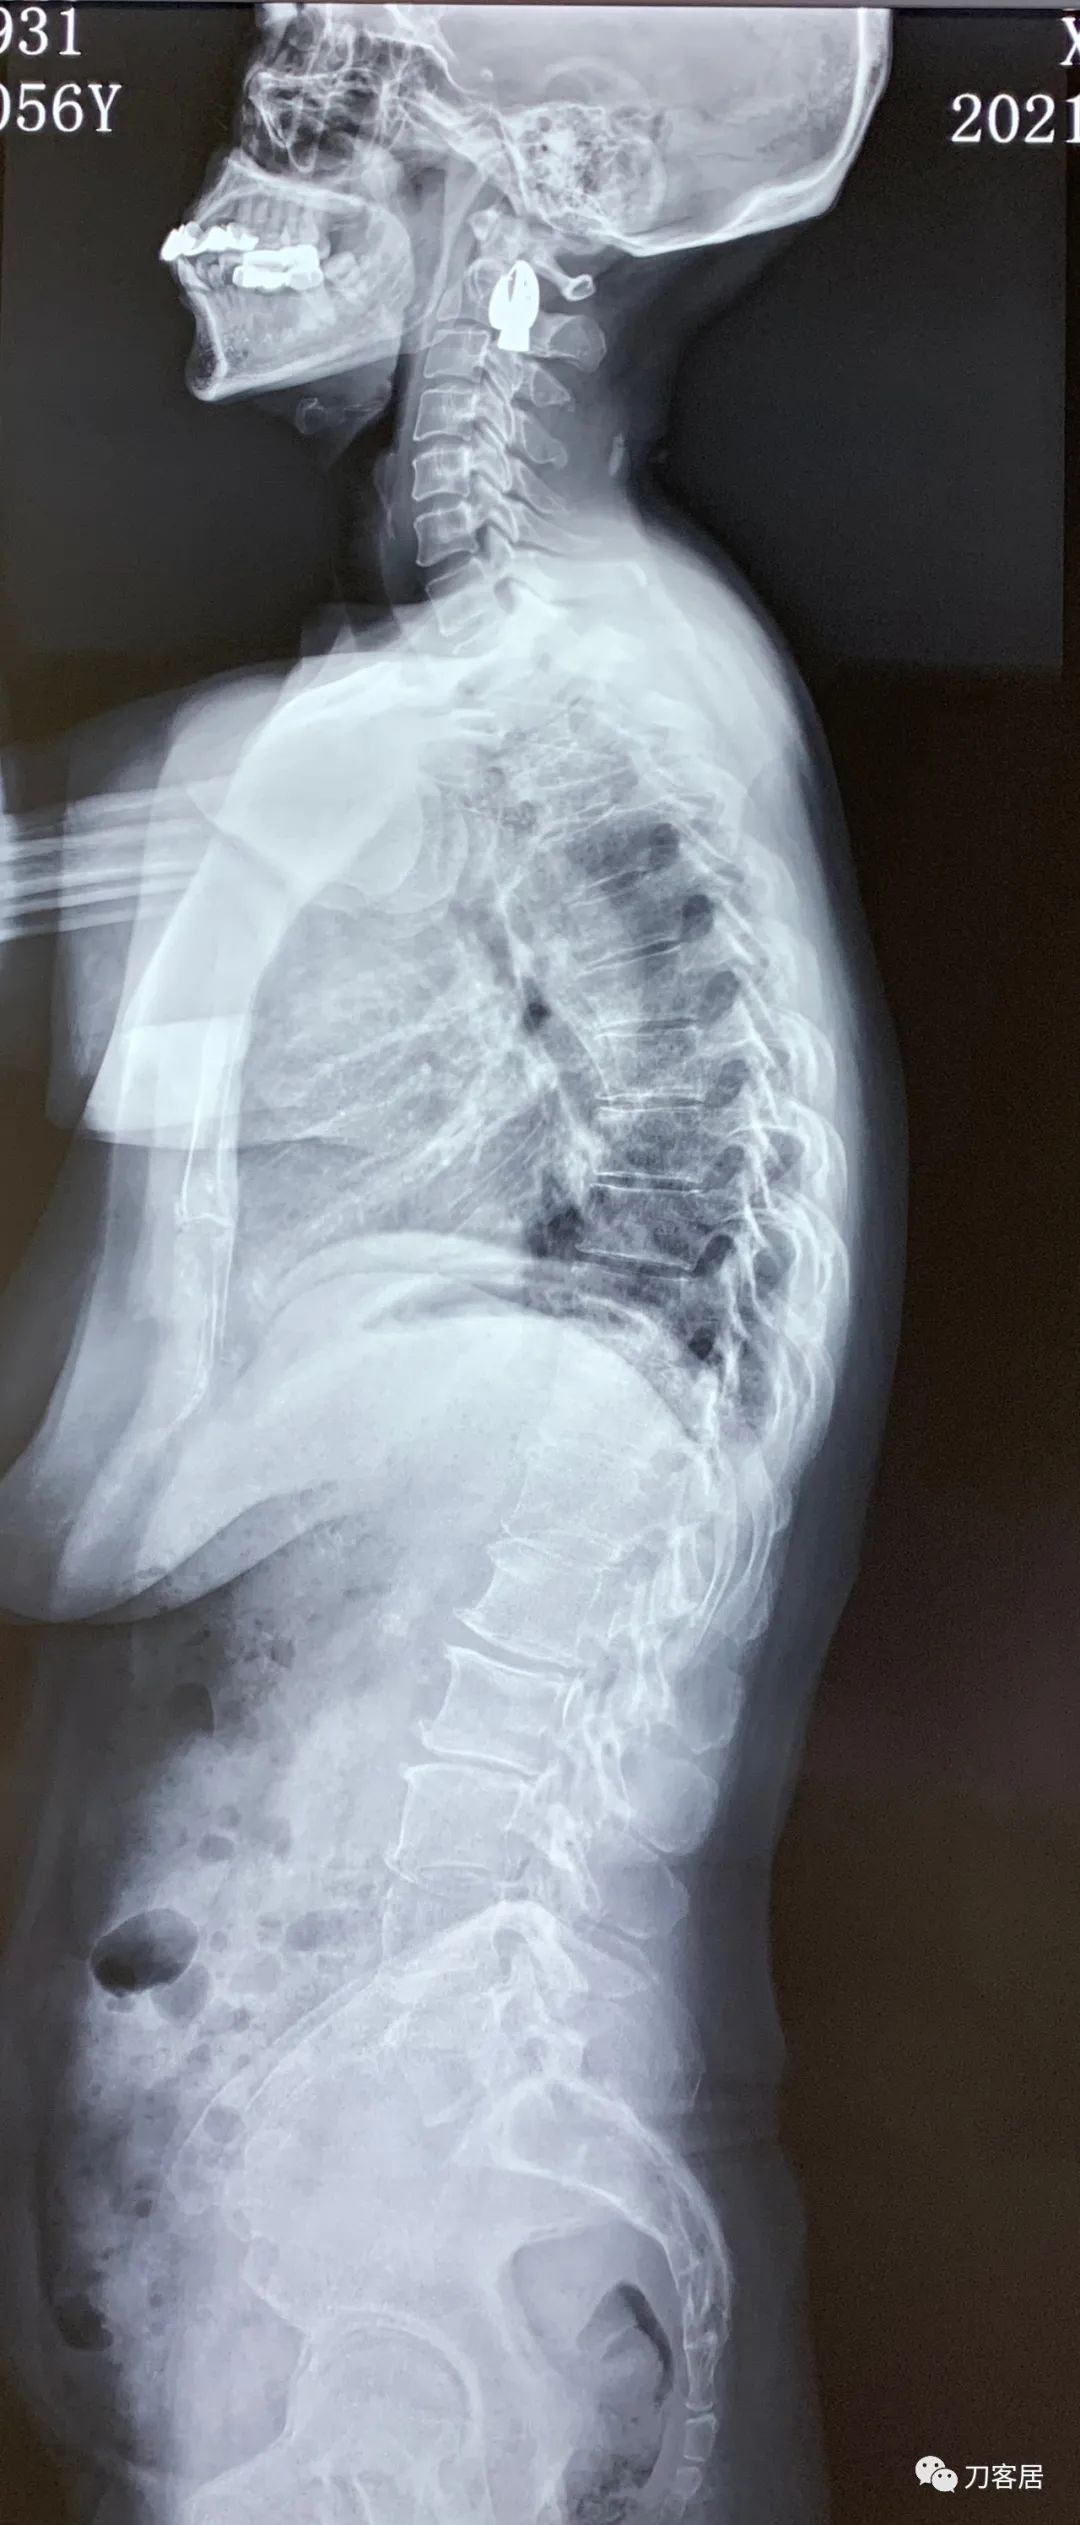

2021年12月12日去渭源县医院做颈椎腰椎MRI,提示1.腰椎侧弯畸形并骨质增生,2. L5S1椎体终板炎(I型), 3. L1-S1椎间盘变性并腰2-4,腰5骶1椎间盘膨出,腰4-5椎间盘突出并相应平面继发性椎管狭窄。2020年12月中旬于渭源县医院行骶管注射2次6针后睡眠改善,

2021年5月17日,西京医院骨科门诊找我就诊,自带影像学检查资料提示腰椎侧弯,腰3-4,腰4-5椎间盘突出,黄韧带肥厚,椎管狭窄。

建议其查双光子骨密度,骨盆正位片以及腰椎间盘平扫。腰椎正侧位X线片以及动力位片,站立位脊柱全长正侧位X线片,以了解其是否有骨质疏松,并了解脊柱侧弯情况,腰椎局部X线表现情况和腰椎间盘突出和椎管狭窄情况。

从这个患者的影像资料分析,颈椎间盘突出问题不大,没有明确的上位神经元损伤表现,所以,不考虑颈椎和胸椎问题。腰椎侧弯畸形,但不严重。因为存在腰椎侧弯,使得腰椎MRI在扫描切面的时候,显示的椎间盘突出或椎管狭窄会有一定的误差,所以,又加做了经椎间盘的CT平扫,影像表现并不严重,综上,腰椎间盘突出,腰椎管狭窄,腰椎侧弯,不考虑手术治疗。同时,患者的主要痛苦是心理疾病,而不是器质性疾病,所以,以心身疾病治疗为主。虽然患者骨密度检查结果提示正常,但X线片显示骨质疏松,且其症状也与骨质疏松的症状有符合之处,比如静息痛,不能入睡,动作及姿势变换时痛加重等,所以,给予实验性抗骨质疏松治疗,以观疗效。